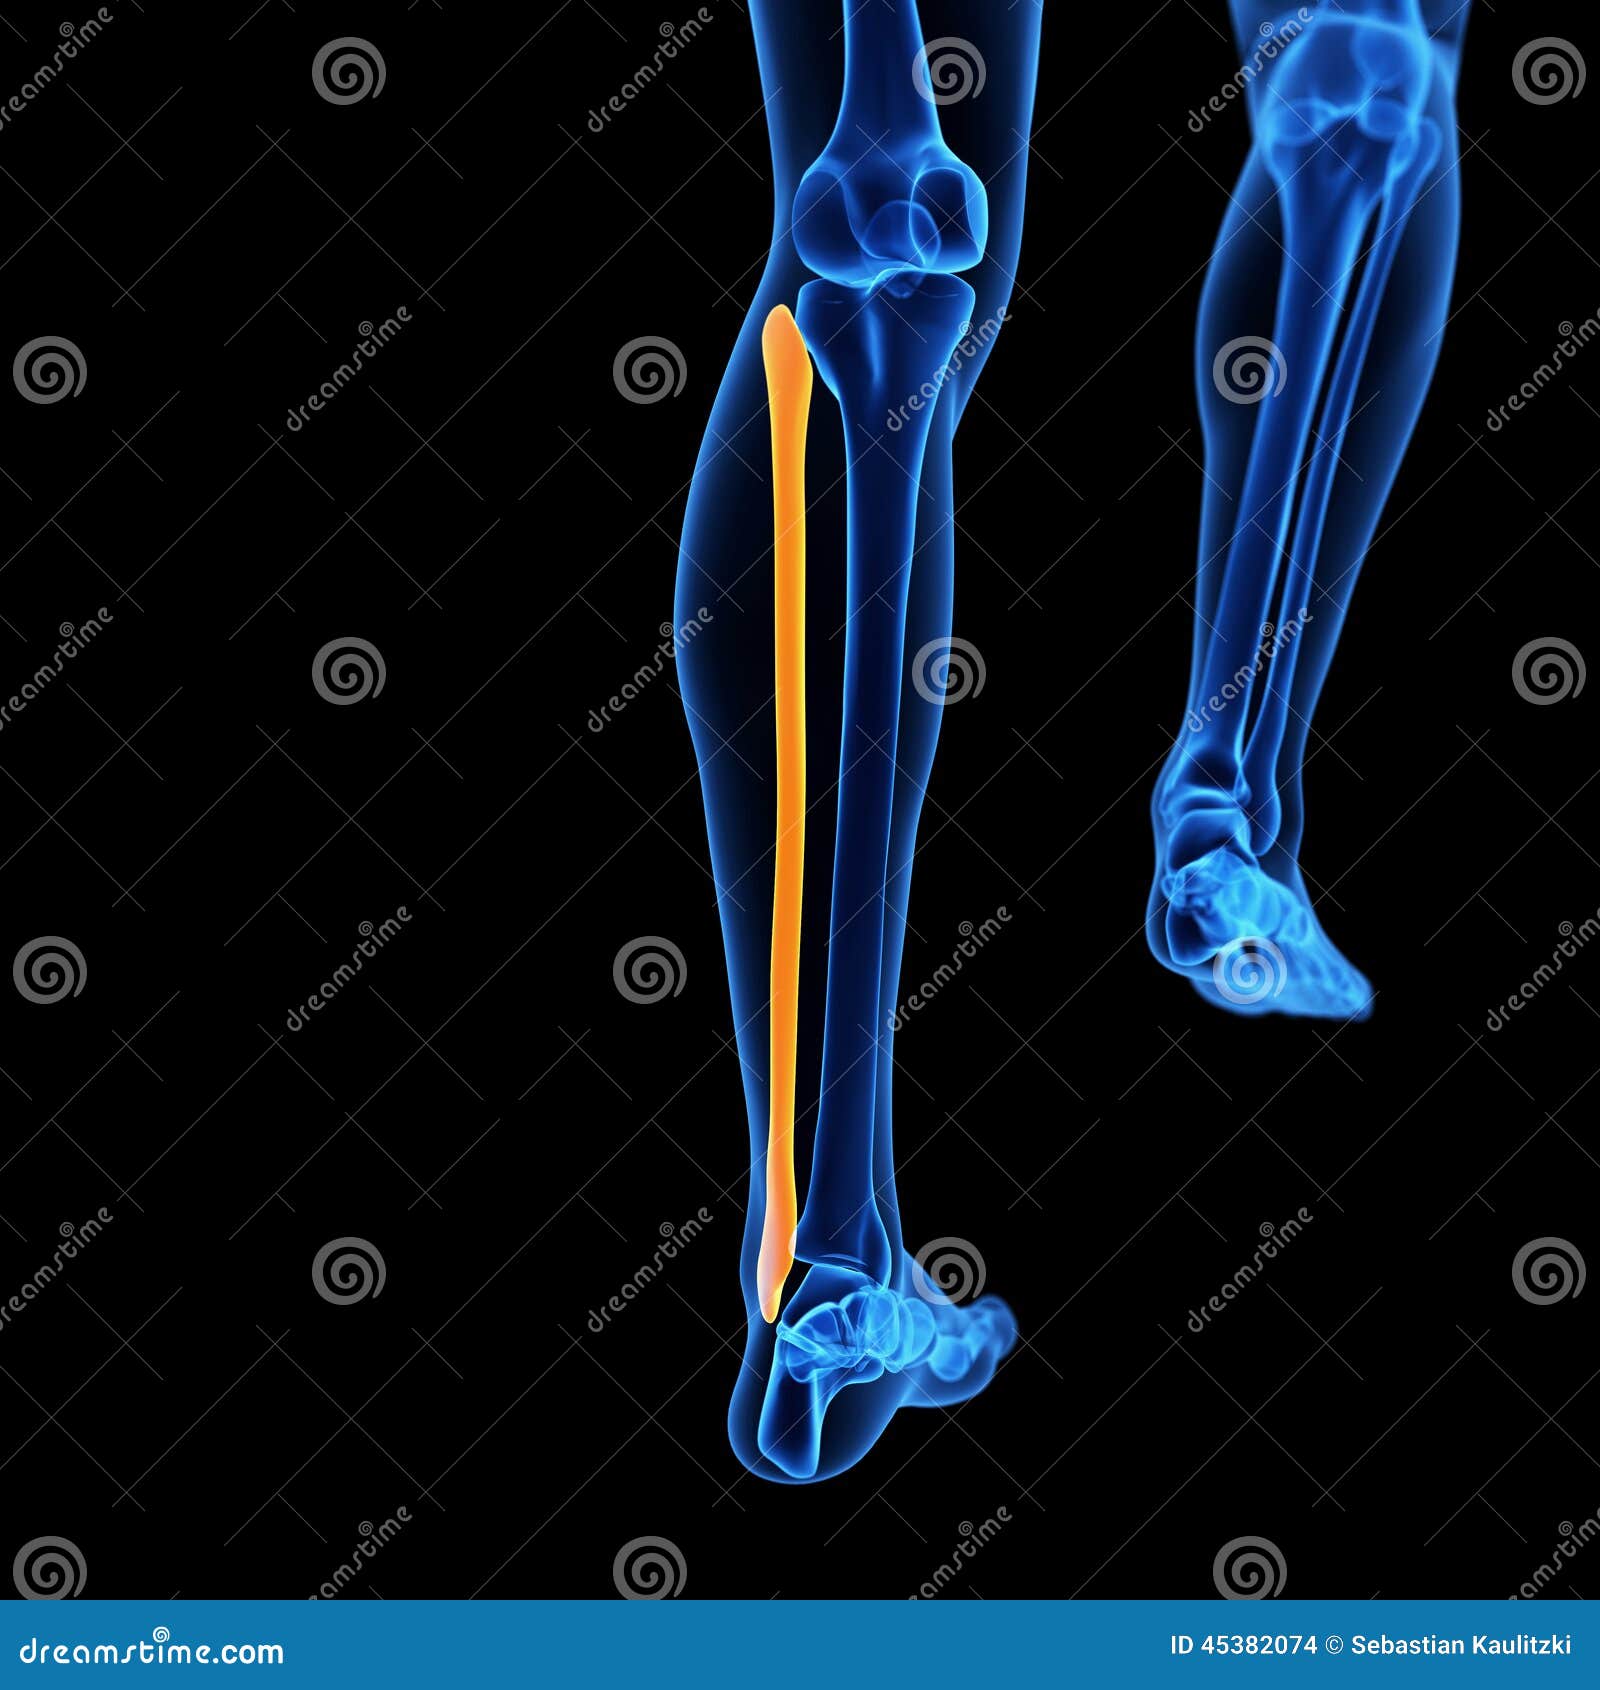

The fibula bone stock illustration. Illustration of skeletal – 45382074

Bone Parallel To Fibula

what bone runs parallel to the fibula